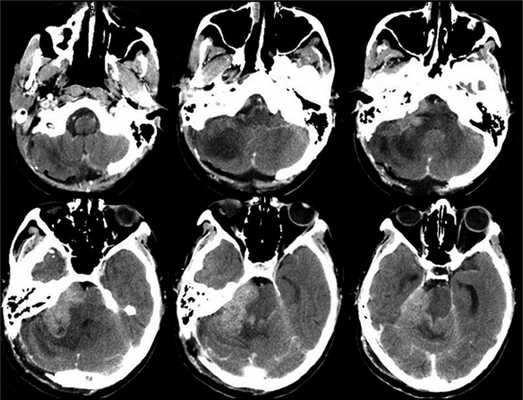

МРТ краниовертебрального перехода и верхнешейного отдела позвоночника больной перед операцией:

МРТ-контроль краниовертебрального перехода и верхнешейного отдела позвоночника у данной больной спустя 8 месяцев после операции (отмечается расширение большой цистерны мозга и уменьшение сирингомиелитической кисты верхнешейного отдела спинного мозга):